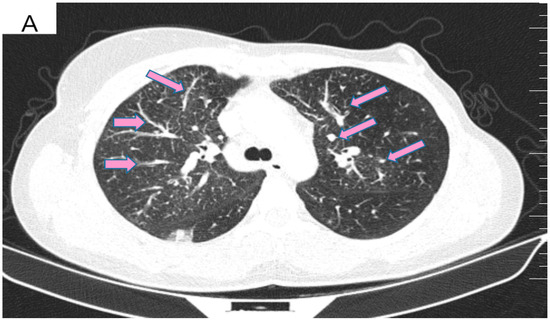

However, 2 years after the initial diagnosis, in February 2021, during the clinical and biological evaluation for an expander replacement, lab reports highlighted abnormal values of the liver enzymes—aspartate aminotransferase (AST) 155 UI/L and alanine aminotransferase (ALT) 114 UI/L. After excluding an infectious or toxic etiology, an abdominal ultrasound revealed the presence of hepatic metastases in the eighth hepatic segment. An abdominal MRI was immediately requested which showed a liver tumor mass of approximately 9.6/6.6 cm with the aspect of liver metastasis (Figure 3A). Subsequently, chest CT revealed carcinomatous lymphangitis (Figure 4A) and millimeter areas of osteolysis in the T1 and L1 vertebral bodies and the sternal body, without brain metastases on cerebral CT. During workup period, the patient’s clinical status worsened by developing symptoms of respiratory failure with dyspnoea at minimal exertion with oxygen saturation (SaO2) of 75% and rapid progressive dry cough. Furthermore, the liver was palpable 6 cm below the costal rim. Hepatic assays were exacerbated by a severe increase in AST 635 UI/L and ALT 309 UI/L (Figure 5), but with normal value of total bilirubin 1.14 mg/dL, alkaline phosphatase 179 U/L and gamma-glutamyl transferase 154 U/L with slightly increased values, albumin 3.01 g/dL, International Normalized Ratio (INR) 1.2. Tumor marker CA 15-3 was also increased (286 U/mL). At that time, the prognosis was extremely reserved.

Figure 4.

(A) Pretreatment CT scan of the lungs showing interlobular septal thickening and multiple bilateral peribronchovascular nodular opacities. (B) CT scan showing resolution of interlobular septal thickening and remission of most of the pulmonary nodules after treatment with six cycles of Pertuzumab, Trastuzumab and Paclitaxel.

After six cycles of treatment, an imaging reassessment revealed the partial remission of liver metastases (Figure 3B), HFN with unchanged appearance, and the favorable evolution of carcinomatous lymphangitis lesions (Figure 4B) and bone metastases. In the absence of neurological symptoms, cranial imaging reassessment was not repeated. Laboratory results were within normal limits, and the CA 15-3 decreased to 33.8 U/mL. During this time, the patient changed her lifestyle, she increased her consumption of fresh fruits and vegetables and fiber and reduced her intake of processed meat, dairy and sugar. Moreover, the increase in physical activity led to gradual weight loss, about 9 kg. This time during treatment, she developed an acneiform rash and onychodystrophy, as well as grade I neutropenia and thrombocytopenia. As a result of the good therapeutic response, Paclitaxel was discontinued and hormone therapy with Fulvestrant was added to dual anti-HER2 monoclonal blockade.